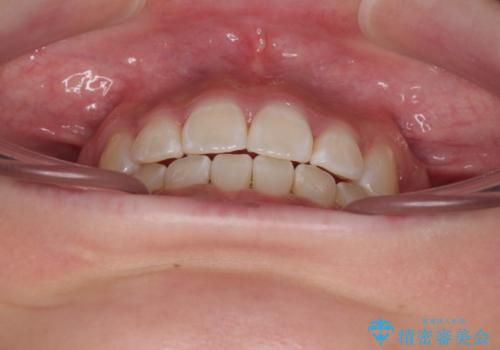

- 口元の突出感と上下前歯のズレを気にして来院された患者様です。

舌の突出癖により上下の前歯は非接触となっている状態でした。

舌のトレーニングをしっかりと行ってくださり、1年半という非常に短い期間で仕上げることができました。